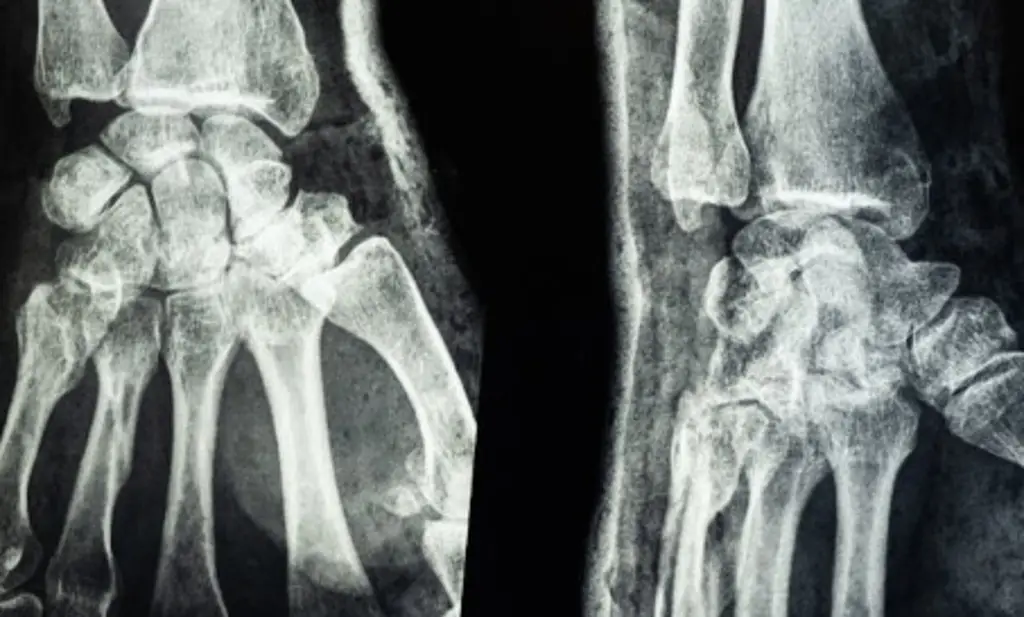

Un equipo de la Facultad de Medicina LKS de la Universidad de Hong Kong (HKUMed) ha desarrollado un innovador material de fosfato de calcio elástico, conocido como "cemento óseo nano", que imita la estructura del hueso humano y promete transformar el tratamiento de fracturas.

Los materiales de fosfato de calcio actuales, aunque biocompatibles, son rígidos, frágiles y no se adaptan a los movimientos diarios, lo que puede causar fallos en la reparación.

El "cemento óseo nano" de HKUMed utiliza tecnología de nano-clústeres para combinar elasticidad, resistencia y tenacidad. Este material se moldea antes de endurecerse, adaptándose a fracturas de formas irregulares.

Al absorber agua, forma microesferas elásticas que rellenan defectos óseos, simplificando cirugías y favoreciendo la regeneración natural del hueso.